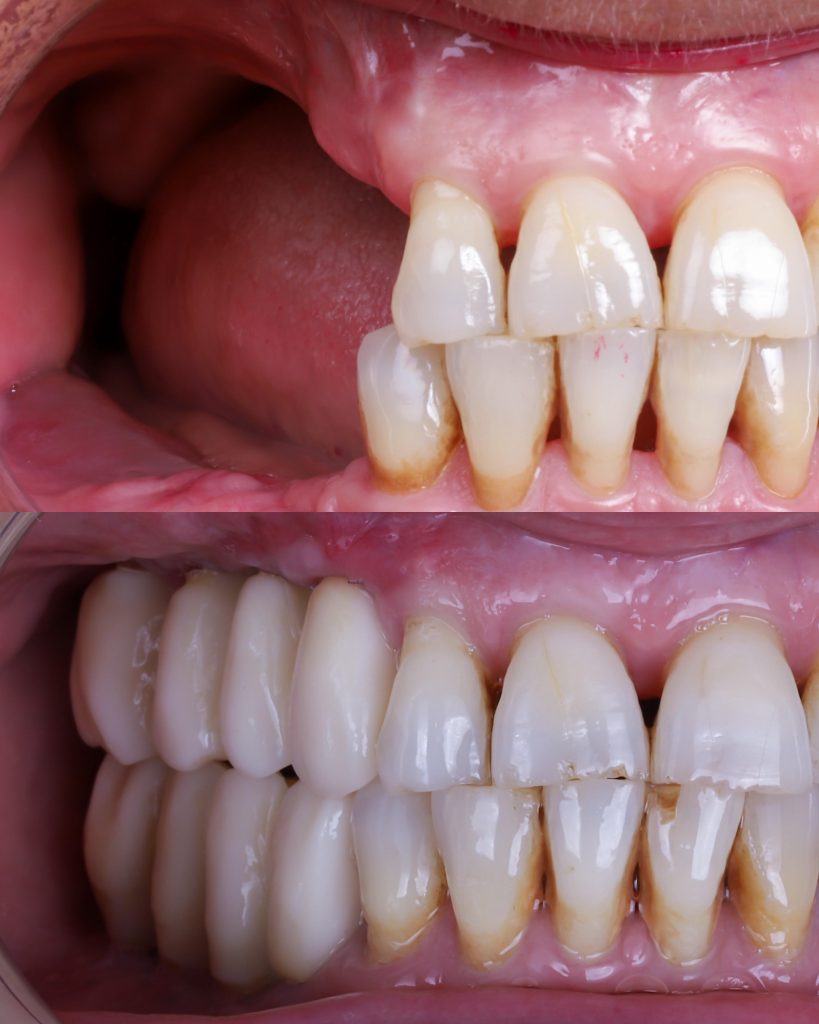

Historias de transformación

Si alguna vez te han dicho que tu caso no tiene solución, en Alejandro Prieto Dental desafiamos los límites de la odontología para ofrecerte la respuesta que estabas buscando.

Before

After

Visualizar la transformación

Los cambios de imagen de la sonrisa favorecen mejoras cuidadosas y matizadas, para obtener resultados naturales que garanticen el equilibrio general y la armonía facial.